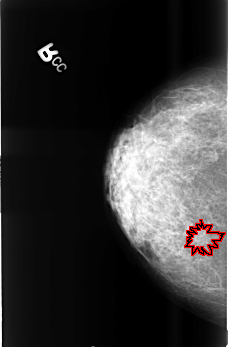

FILE: B_3399_1.RIGHT_CC.OVERLAY

TOTAL_ABNORMALITIES 1

ABNORMALITY 1

LESION_TYPE CALCIFICATION TYPE PUNCTATE DISTRIBUTION CLUSTERED

LESION_TYPE MASS SHAPE ARCHITECTURAL_DISTORTION MARGINS ILL_DEFINED-SPICULATED

ASSESSMENT 4

SUBTLETY 3

PATHOLOGY MALIGNANT

TOTAL_OUTLINES 1

BOUNDARY

RIGHT_CC LINES 4504 PIXELS_PER_LINE 2952 BITS_PER_PIXEL 12 RESOLUTION 50 OVERLAY